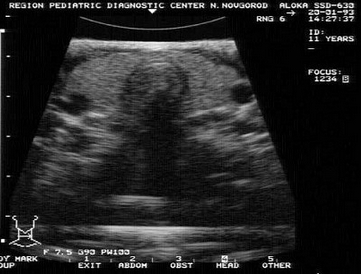

15、单项选择题

根据超声图像所示,该病例为哪型肾积水()